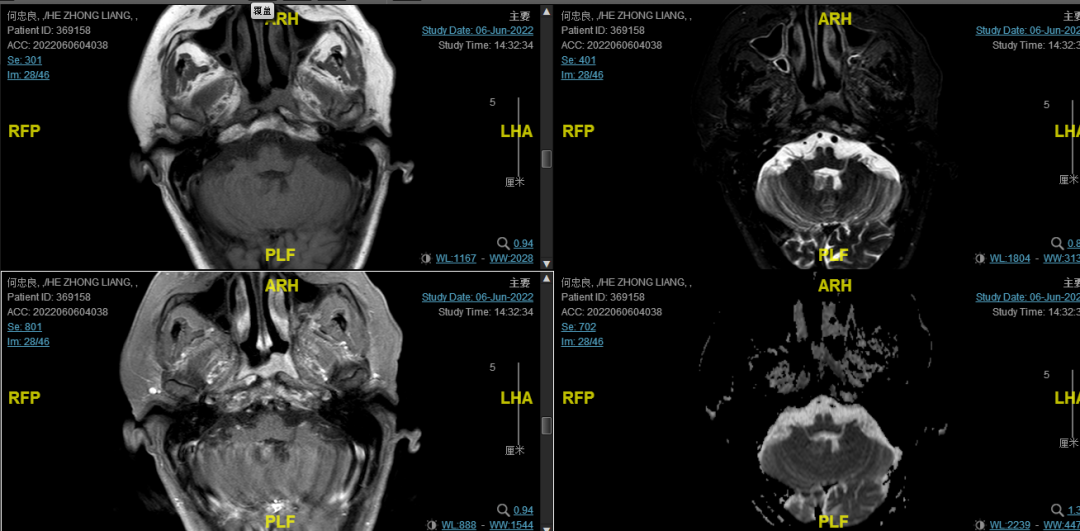

后患者至江苏省肿瘤医院放疗科就诊,2022-06-06完善头颅MR检查:

修正诊断:鼻咽癌T3N1M0,Ⅲ期。

2022-08-05(放疗近结束)复查MR,疗效评价:CR。鼻咽部肿物及咽后转移淋巴结颈部转移淋巴结均达到CR。